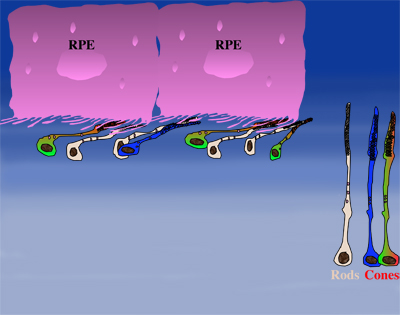

How could the observations of nutritionally deprived cones explain the dependence of cones on rods? Photoreceptor outer segments interact with the retinal-pigmented epithelium, which a single sheet of cells adjacent to the photoreceptor layer. The outer segments-retinal-pigmented epithelium interactions are vital since the retinal-pigmented epithelium provides nutrition and oxygen to PRs. Roughly 95% of all PRs in mouse and human are rods and approximately 20-30 outer segments contact one retinal-pigmented epithelium cell. Thus, only 1-2 of those retinal-pigmented epithelium-outer segment contacts are via cones. In Retinitis Pigmentosa rods die primarily due to a mutation in a rod specific gene. The loss of rods, which comprise ~95% of all photoreceptors leads to a collapse of the outer nuclear layer. During this collapse, the few remaining cone:retinal-pigmented epithelium interactions are likely perturbed (Rollover image below). If these interactions drop below a critical threshold required for the proper flow of nutrients, the loss of rods results in reduced flow of nutrients to cones. By cross-comparing 4 mouse models of Retinitis Pigmentosa we found in our studies that cone death starts always after ~90% of rods have died. This cell density thus represent the crucial threshold of remaining cells after which flow of nutrition is perturbed. This mechanism also explains why the loss of cones does not lead to rod death. Since in humans and mouse, cones are less than 5% of all PRs, the critical threshold that perturbs outer segment-retinal-pigmented epithelium interactions is not be reached. Additionally, it also explains why in cone rich species such as Zebrafish loss of cones does affect rod survival. In summary, the determining factor for the less abundant photoreceptor cell type to die when the more abundant one dies, is the local ratio between the 2 photoreceptor cell types.

| During rod cell death the cell density decreases in the outer nuclear layer (rollover first panel to see the number of rods decrease). The reduced number of rods in the outer nuclear layer results in a collapse of the ONL and put stress on the outer segment retinal-pigmented epithelium interactions (rollover second panel to detach the outer segments from the retinal-pigmented epithelium). At later stages of degeneration a retinal cross-section looks similar to what is seen in the last panel. Once this critical threshold of remaining cells is breached cones start to die due to reduced nutrient flow while the remaining rods die due to the intrinsic mutation. | ||